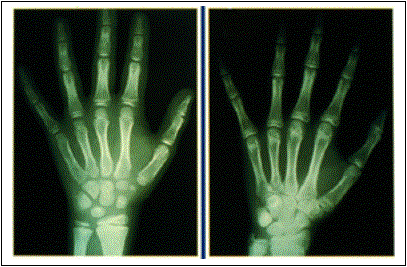

Ao lado podemos ver duas radiografias que foram feitas para avaliar a idade óssea. A radiografia da esquerda é de um menino de 8 anos e a da direita é de um menino de 14 anos. Nota-se, sobretudo no punho (fica na base da mão, aonde tem um aglomerado de ossinhos), que os centros de ossificação estão mais avançados à direita.